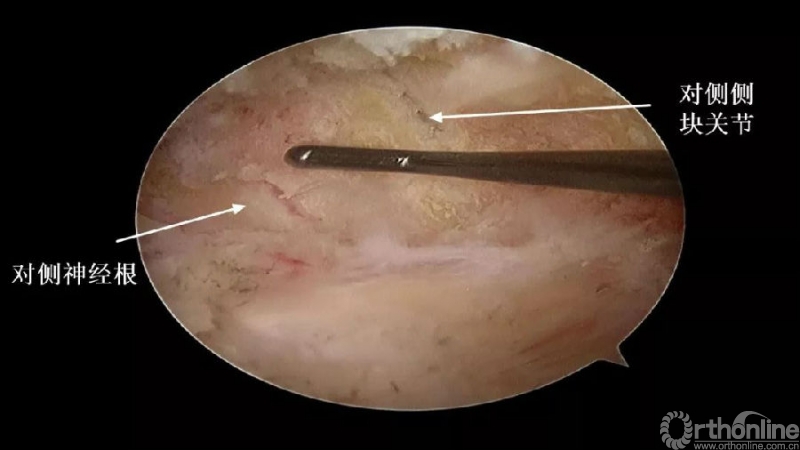

4.进一步加深移除骨赘的残余部分,直到显露出对侧的神经根及关节突关节的内壁;